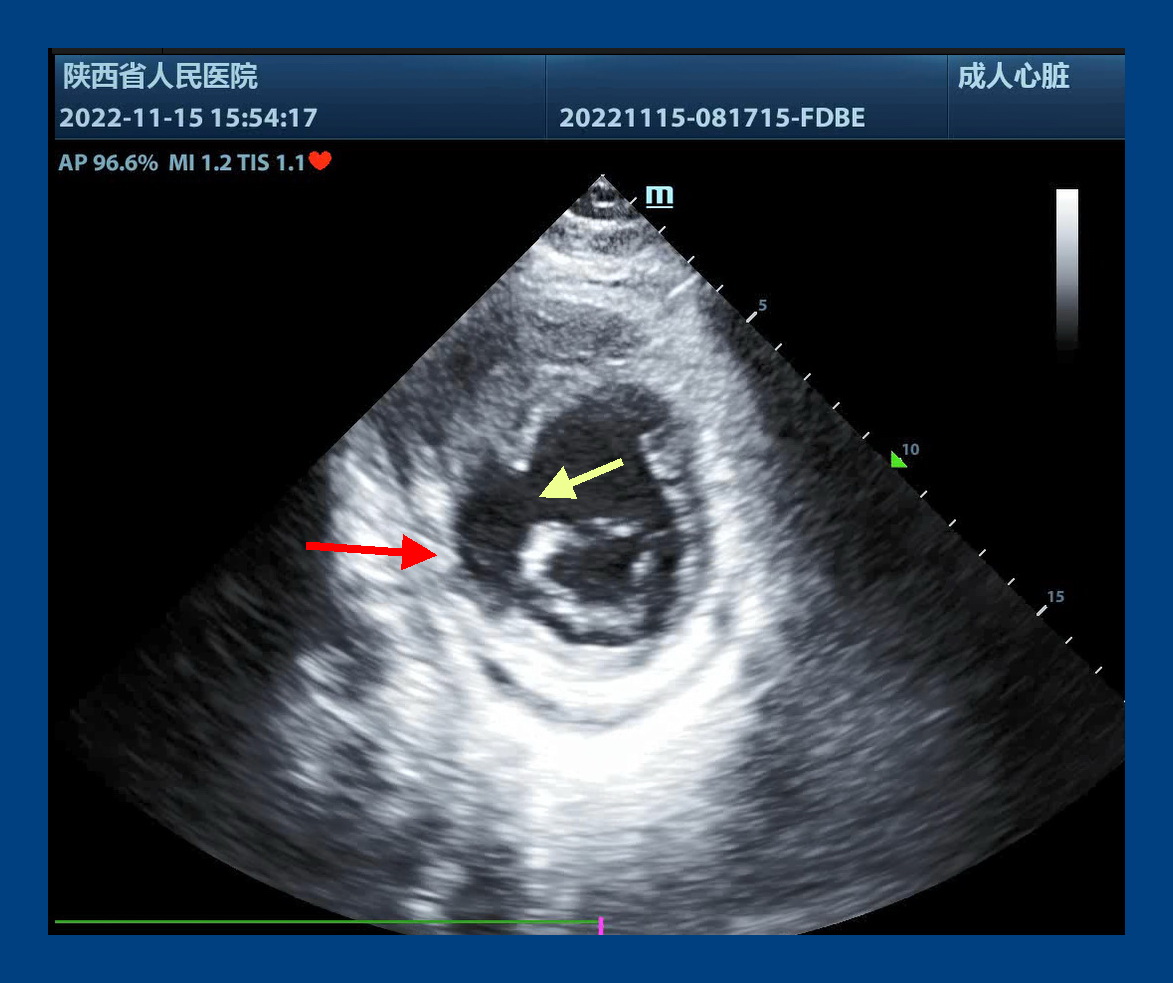

当地医院专家立即与六合彩网站心脏内科梁磊主任联系后,立即将患者转入六合彩网站心脏外科,付建莉主任医师心脏超声检查,确诊为心脏左室下壁瘤样膨出,与正常室壁呈矛盾运动,测其瘤口为41mm,瘤深27mm,后室间隔下壁回声失落,左室面缺损口大小38mm,右室面缺损口大小21mm,病情十分危急。

心包切开后,发现大量血性心包积液,室壁瘤已经发生破裂,心脏严重水肿,经室壁瘤切口探查,发现一个近30毫米的巨大室间隔穿孔。术后经食道超声证实,室间隔穿孔消失,左心室前侧壁和下壁活动度改善,瓣膜未见反流。手术顺利结束,患者安全回到心外科ICU。